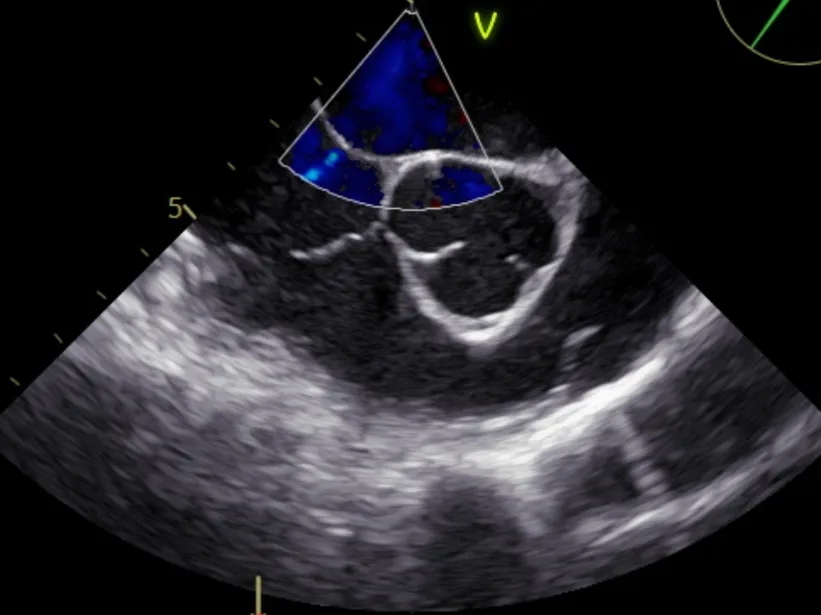

术中发泡试验确认

术中再次进行发泡试验:右心气泡充满后,左心未发现气泡,封堵效果良好。